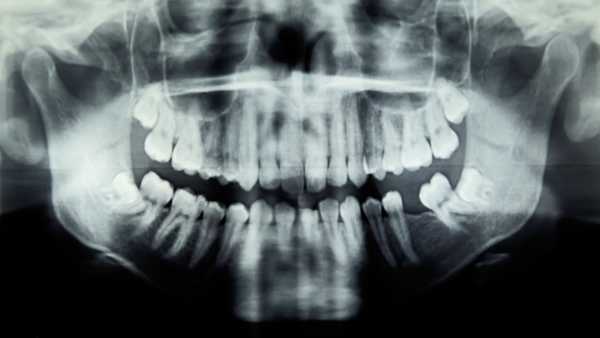

Симптоми: Пацієнтка протягом кількох тижнів відчувала задишку під час фізичної активності, коли звернулася до лікарні для обстеження. У неї також було в анамнезі виділення незвично темної сечі, що відбувалося з дитинства, а у 40 років їй зробили повне ендопротезування кульшового та колінного суглобів з обох боків через артрит.

Що робить цей випадок унікальним: До поширених факторів ризику аортального стенозу належать високий рівень холестерину, високий кров'яний тиск або куріння в анамнезі. Цей стан часто збігається з ішемічною хворобою серця, яка характеризується накопиченням бляшок в одній або кількох артеріях, що постачають кров до серця. У випадку цієї пацієнтки коронарні артерії виглядали нормальними, але лікарі виявили щось незвичайне під час операції на відкритому серці: «чорну пігментацію» та кальцифіковані «темно-чорні» тканини в аорті та аортальному клапані відповідно.

Тканину, видалену під час операції, додатково дослідили під мікроскопом. Це дослідження виявило «відкладення коричневого пігменту» в затверділих ділянках аортального клапана та в деяких некальцифікованих тканинах структури. У затверділій тканині клапана команда також виявила ознаки хронічного запалення, включаючи наявність імунних клітин, «навантажених пігментом». Також спостерігалася дегенерація в сполучних тканинах клапана.

На основі цих висновків, а також історії хвороби пацієнтки, лікарі визначили, що в неї рідкісне генетичне захворювання, яке називається алкаптонурія. Вважається, що в усьому світі це спадкове захворювання вражає від 1 з 250 000 до 1 з 100 000 людей, хоча поширеність значно варіюється в різних країнах.

Алкаптонурія спричинена мутаціями в гені HGD, який містить інструкції для ферменту, що допомагає розщеплювати два білкові будівельні блоки в організмі: фенілаланін і тирозин. Ці мутації роблять фермент менш ефективним, що призводить до накопичення побічного продукту фенілаланіну та тирозину. Побічний продукт, гомогентизинова кислота, виводиться з сечею, через що сеча потемніє під впливом повітря. А у людей з алкаптонурією гомогентизинової кислоти забагато, щоб організм міг її вивести, тому речовина накопичується в сполучних тканинах.

Кислота, що накопичується, перетворюється на «охронотичний пігмент», який по суті забарвлює тканини, де він накопичується, і зрештою кальцифікується або твердне. Багатьом людям з алкаптонурією потрібне ендопротезування суглобів, оскільки їхні суглоби кальцифікувалися, а у деяких людей це кальцифікування також впливає на серце. Так сталося з 65-річною жінкою.